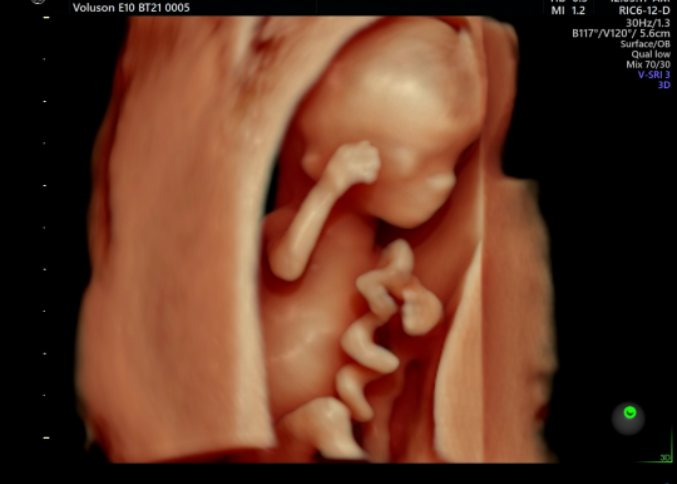

孕妇彩超

孕妇彩超是一种超声检查。美国GE-E10高端四维彩超可以执行胎儿头部和脸部的立体成像。它可以清楚地显示眼睛、鼻子、嘴巴、腹等状况,并可以帮助医生直接诊断胎儿先天性畸形,包括表面畸形,内脏畸形和面部和面部畸形,可以确定胎儿在子宫中的确切位置。

四维彩色多普勒超声在功能的基础上还增加了时间维度参数,并且可以实时观察胎儿动态的运动图像,能够更加清晰的筛查胎儿在子宫内的状态,筛查胎儿是否有异常,提供准确的科学依据,及早发现、及早作出解决方案。